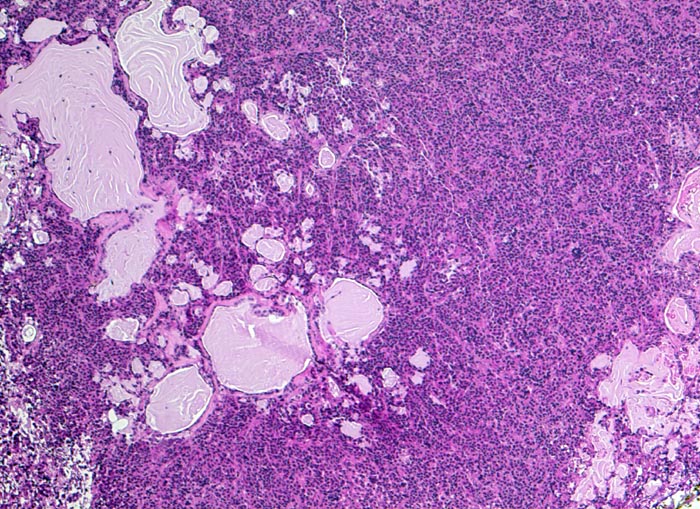

AP/ Prolaktinom

Prolaktinom

Hypophyse, Vorderlappen